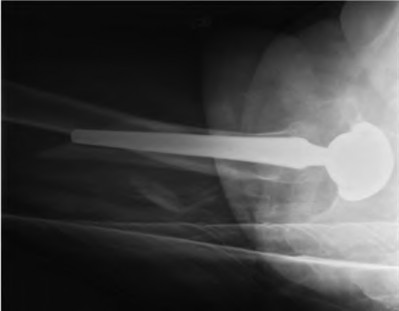

Question 9:

A 55-year-old highly active man is scheduled for a total hip arthroplasty (THA). The surgeon considers utilizing a ceramic-on-ceramic bearing surface to maximize longevity. Which of the following is the most notable disadvantage or complication specific to a ceramic-on-ceramic bearing compared to ceramic-on-highly cross-linked polyethylene?

Correct Answer: Audible squeaking during hip articulation

Explanation:

Ceramic-on-ceramic (CoC) bearings offer the lowest wear rates of all THA bearing couples and do not cause significant osteolysis or metal-related hypersensitivity. However, a well-documented unique complication of CoC bearings is audible squeaking during motion, occurring in up to 10-15% of patients in some series, often associated with micro-separation or impingement.